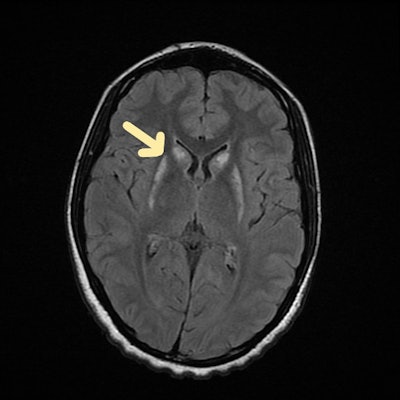

Carbon monoxide poisoning. Brain MRI scan (axial FLAIR sequence) shows periventricular hyperintensities. All images courtesy of Dr Gurubharath Ilangovan et al and the ESR's EPOS database.

Carbon monoxide poisoning. Brain MRI scan (coronal FLAIR sequence) shows symmetric hyperintense foci in the globus pallidus.

In these patients, CT shows low attenuation in the globus pallidus. On MRI, the medial portions of the globus pallidus appear as bilateral areas of low signal intensity on T1-weighted images and of high signal intensity on T2-weighted and FLAIR images. The degree of carboxyhemoglobin and the range or intensity of MRI results do not appear to be related.